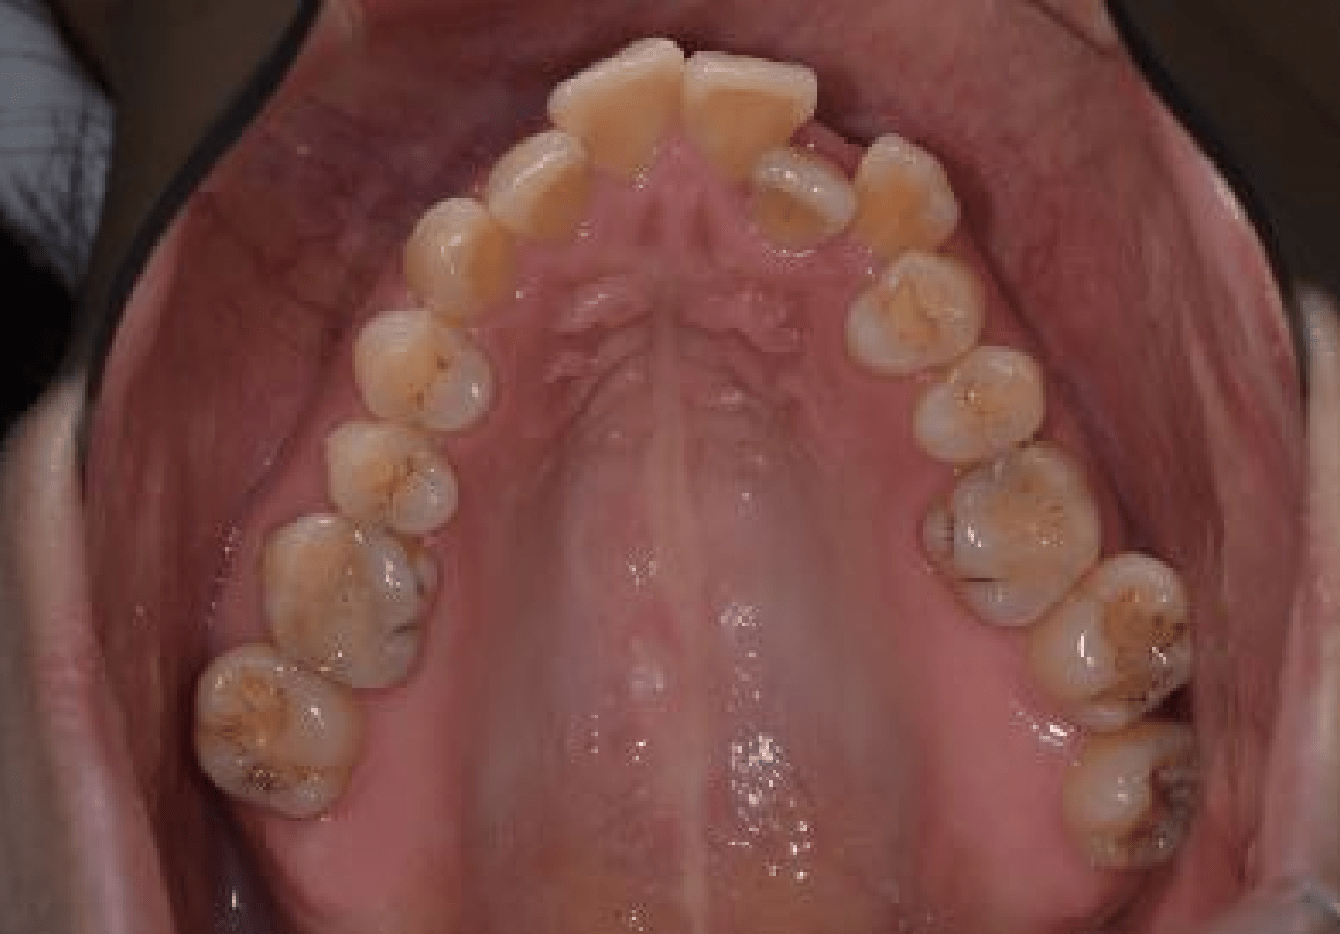

ガタガタな歯並びを改善したい

この患者様は、ガタガタの歯並びを治したいという主訴で来院されました。

二級咬合(いわゆる出っ歯)に分類され、叢生もあります。写真で見ると、側方の写真では前歯が出ていて、正面から見ると互い違いのは並びになっているように見えます。

外科治療前の状態

外科治療前の状態です。上下のアーチは綺麗になっているものの、側方から見るとオーバージェットの状態が残っています。